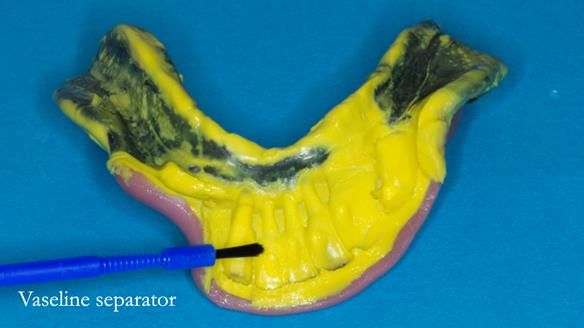

An honest note on the impressions

It’s important to say that I struggled considerably to obtain accurate impressions of Ken’s lower anterior teeth. This was a difficult situation and not one that went smoothly.

At one stage, a tray became locked in position and had to be sectioned and removed carefully. This is not something I like but it does happen, particularly in cases with long, thin teeth and compromised anatomy.

Instead, we made a Scandinavian-style, metal-based lower RPD.

It was made promptly, then relined gradually over the following year

to optimise fit, comfort, and support.